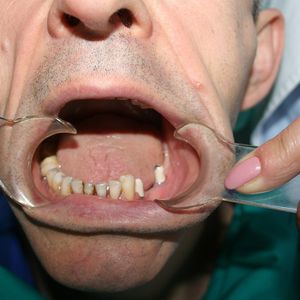

Surgical placement: the implant is inserted into the jawbone under local anaesthesia. The procedure is minimally invasive and typically painless.

Prosthetic rehabilitation: once osseointegration is complete, an abutment and permanent crown, bridge, or denture is placed on the implant. Prosthetic rehabilitation on implants is our core specialty and is key to the long-term success of the treatment.